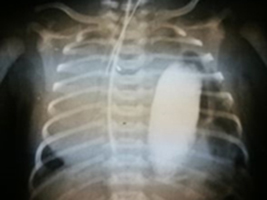

ChirurgiaWrodzona przepuklina przeponowa (WPP) to rzadka wada, w której występuje patologiczny ubytek w przeponie. Skutkiem tego jest przemieszczenie narządów jamy brzusznej do klatki piersiowej przez otwór w przeponie powstały między 3 a 8 tygodniem embriogenezy, co może prowadzić do jedno- lub obustronnej hipoplazji płuc, nadciśnienia płucnego i niewydolności oddechowej, która bezpośrednio zagraża życiu noworodka [1,2]. Wada występuje z częstością 2,4-4,9 na 10 000 urodzeń [3]. Najczęściej występuje przepuklina tylno-boczna (Bochdaleka), głównie lewostronna – 84% przypadków, rzadziej przepuklina przymostkowa (Morgagniego) zwykle prawostronna – 14% przypadków, jeszcze rzadziej obustronna – ok 2% przypadków [4]. Zastosowanie prenatalnego badania USG pozwala obecnie na wczesne wykrycie opisywanej wady, dając możliwość szybkiego zastosowania odpowiedniego leczenia noworodka co znacząco pozwala ograniczyć śmiertelność do 40% przypadków [5]. <br /><br />Przedstawiamy przypadek pacjenta, operowanego w 4 dobie życia z powodu wrodzonej przepukliny przeponowej wykrytej tuż po urodzeniu. U pacjenta zdiagnozowano nawrót przepukliny w wieku 21 lat, mimo wcześniejszego odpowiedniego leczenia w okresie noworodkowym. Z powodu wieku chorego i nieswoistych objawów, prezentowany przypadek nawrotu przepukliny przeponowej stanowił trudność diagnostyczną.<br />